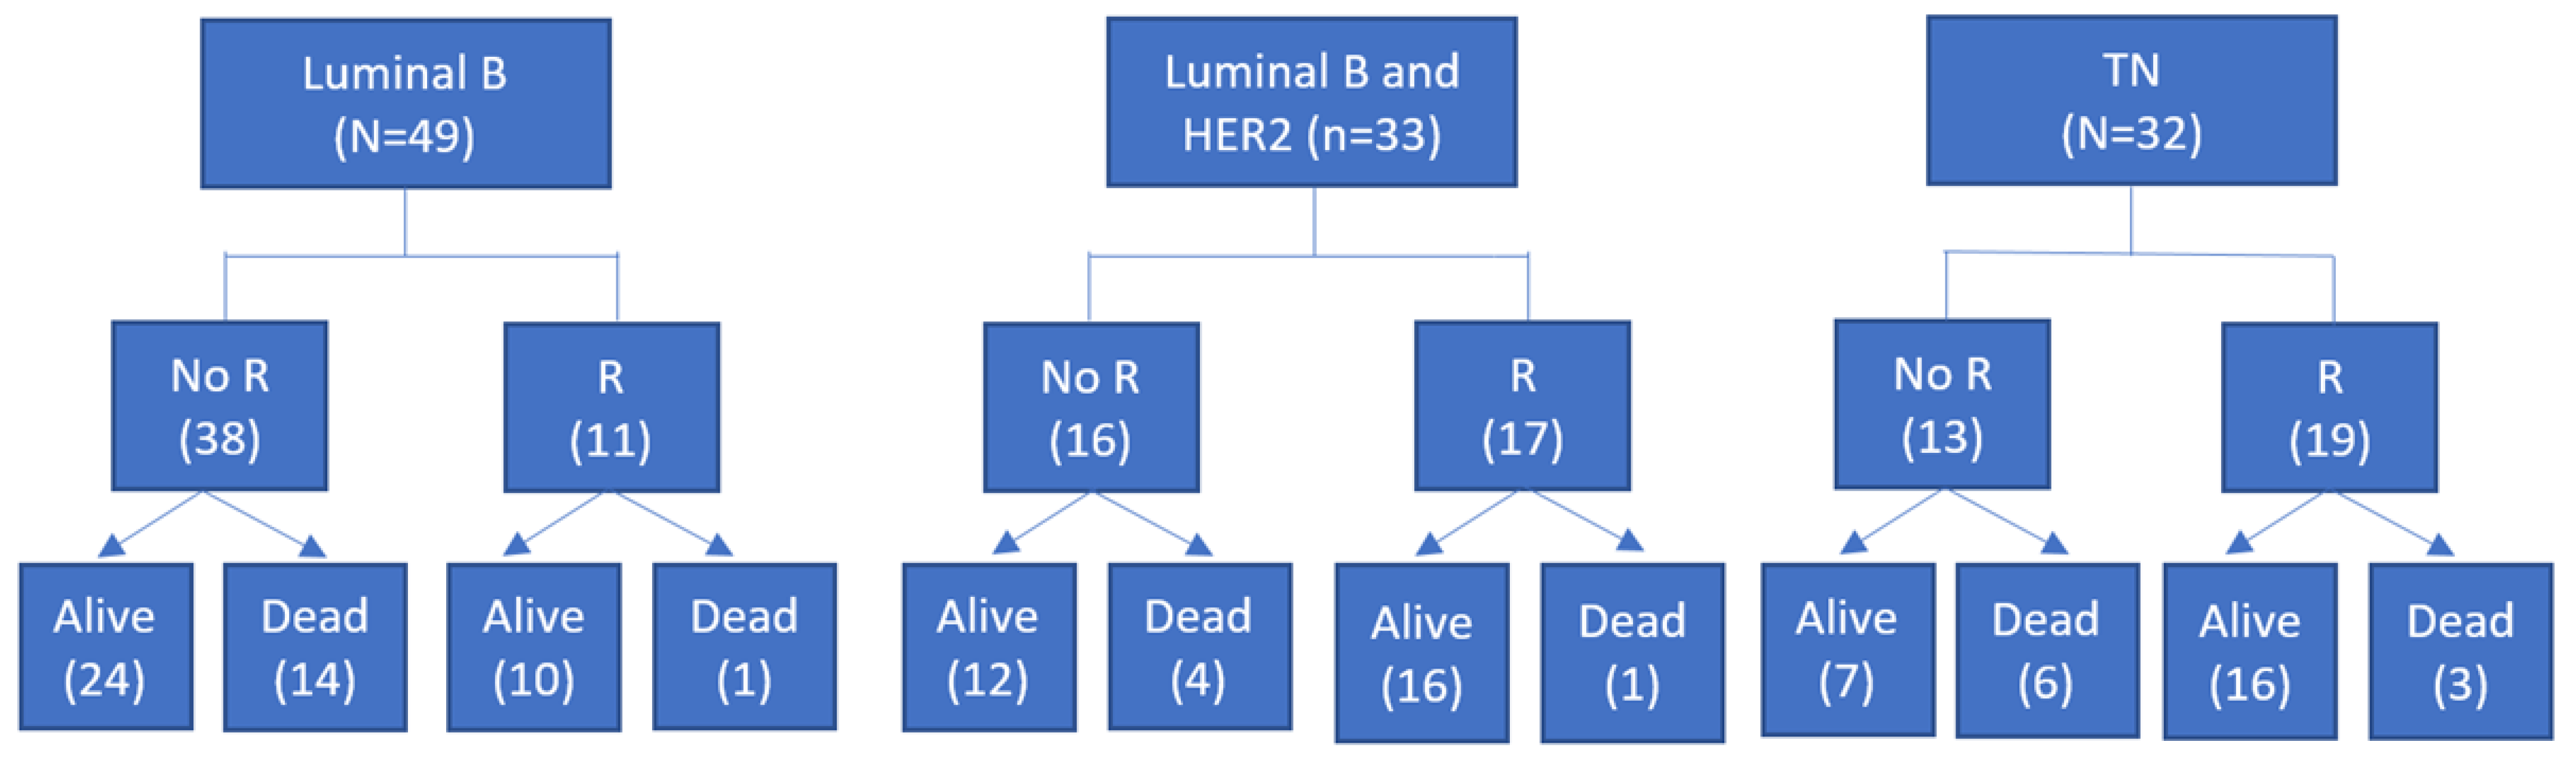

| pCR after NAC No Yes | 38 (77.6%) 11 (22.4%) | 16 (48.5%) 17 (51.5%) | 13 (40.6%) 19 (59.4%) |

| TNBC with pCR after NAC | |||

| Alive | Dead | P Value | |

| MTV_B | 7.5 ± 9.9 | 35.2 ± 34.1 | 0.009 |

| TLG_B | 85 ± 125 | 317 ± 355 | 0.039 |

| MTV_WB | 12.8 ± 15.2 | 43.2 ± 26.7 | 0.012 |

| TLG_WB | 105.1 ± 131.4 | 360.1 ± 286.4 | 0.020 |